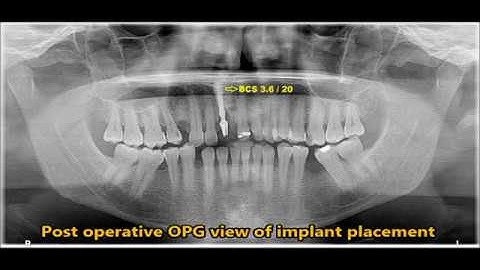

Fractured central incisor Extraction and immediate basal implant for immediate loading